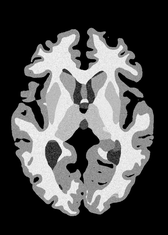

4.2 Registration to a 100 micron ex-vivo brain MRI volume

To showcase the efficacy of our method on real large scale images, we register a 250 in-vivo MRI image (Lüsebrink et al., 2017) to a 100 ex-vivo FLASH human brain volume (Edlow et al., 2019). This represents an inverse problem with more than 11.2B optimizable parameters (compared to 20M for clinical datasets), or 44.8GB of GPU memory. The entire problem does not fit on most GPUs, necessitating distributed multimodal registration. We optimize a composite transform - affine followed by a diffeomorphic mapping; details can be found in Section E.1. Multimodal deformable registration took 58 seconds on 8 NVIDIA A6000 GPUs, which is unprecedented at this resolution. Fig. 6 shows qualitative results, highlighting the ability to register highly detailed structures such as cerebellar white matter; these structures are not visible at macroscopic scales. The resultant advantages of performing registration at this scale can allow researchers to characterize the neuroanatomy at microscopic resolutions and allow morphometric analysis of cortical layers and subcortical nuclei among other structures.